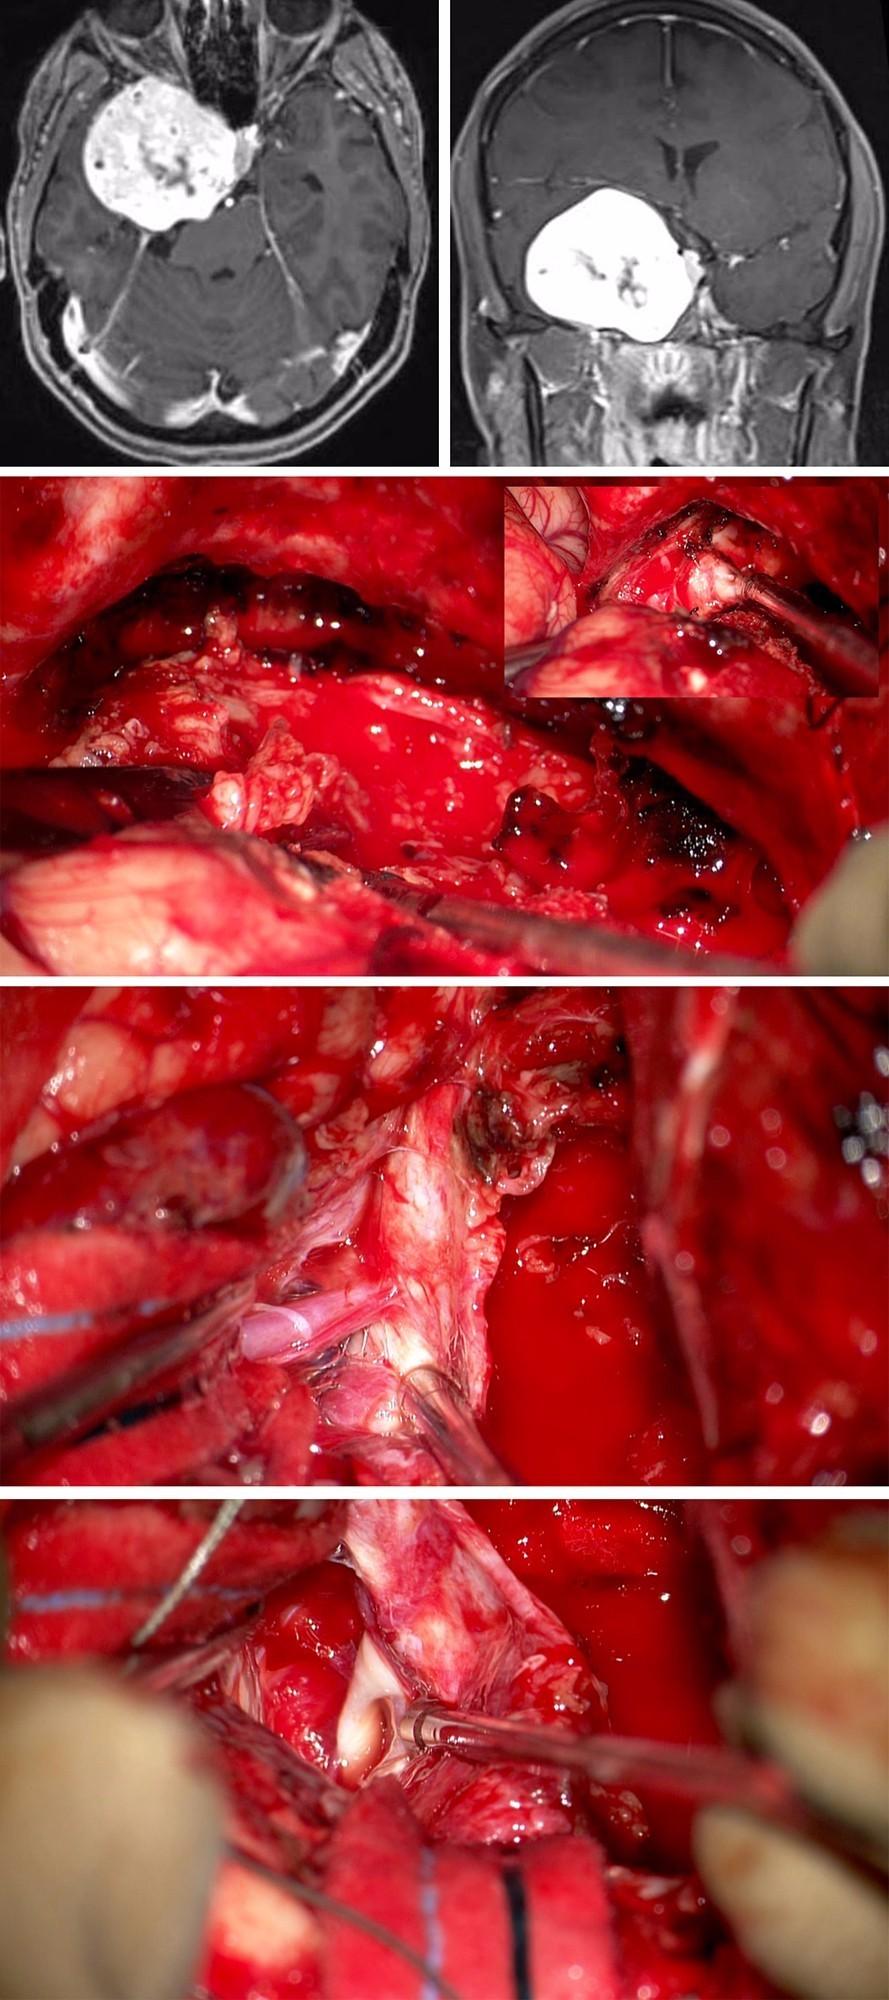

病例

54岁女性,表现为进行性面部麻木。

图13:第一排图片为该巨大海绵窦脑膜瘤的影像。以右侧扩大翼点入路开颅。由于肿瘤体积巨大,故采用硬膜内-外联合入路。硬膜内入路切开海绵窦外侧壁(第二排图片),肿瘤减压,可辨认三叉神经(插图)。切除窦壁的肿瘤,可见大脑中动脉分支粘连(第三排图片)。近全切肿瘤后,可见动眼神经(第四排图片)。